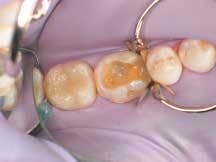

For the Class II restoration on Tooth No. 19, a thin layer of flowable composite (4 Seasons Flow) was applied in the gingival box area, as well as any other deep preparation areas, and cured for 20 seconds using a curing light at ≥500mW/cm2. For the restoration build-up on Teeth Nos. 17 through 19, each cusp area was developed using .5 mm to 1 mm increments of the A 3.5 dentin shaded composite, building each increment out in a cup-like manner (i.e., as described by Lee Culp, CDT), rather than lobing the cusps. Each increment was then "tack cured" through the tooth for five seconds per increment through whichever cusp had been built up (Figure 3).

3